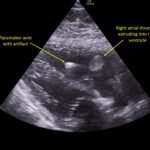

A 78-year-old gentleman presented to the emergency department (ED) for palpitations and dizziness. He had a complicated medical history including atrial fibrillation (AF), recently status post a Watchman procedure, oxygen-dependent chronic obstructive pulmonary disease (COPD), and heart failure with preserved ejection fraction (HFpEF). Point-of-care ultrasound (POCUS) revealed the presence of an intracardiac right atrial thrombus. Computed tomography (CT) angiography confirmed the presence of multiple pulmonary emboli (PE), and extension of the thrombus into the inferior vena cava. Pulmonary emboli are a common complication of thrombus in the right atrium. Management may include anticoagulation, thrombolysis, or thrombectomy. This case highlights that emergency physicians can expedite the diagnosis of intracardiac thrombus by using POCUS. The case presented describes a medically complex patient presenting with symptomatic right intracardiac and inferior vena caval thrombosis complicated by multiple PE. Point-of care ultrasound of the heart and lungs were included in his initial assessment, revealing findings of an intracardiac thrombus, and ruling out multiple other differential diagnoses including pericardial tamponade, pleural effusion, pulmonary edema, and pneumothorax. This finding changed the trajectory of this patient’s evaluation and management, and demonstrates the important role of POCUS in the care of ED patients with undifferentiated cardiopulmonary symptoms.